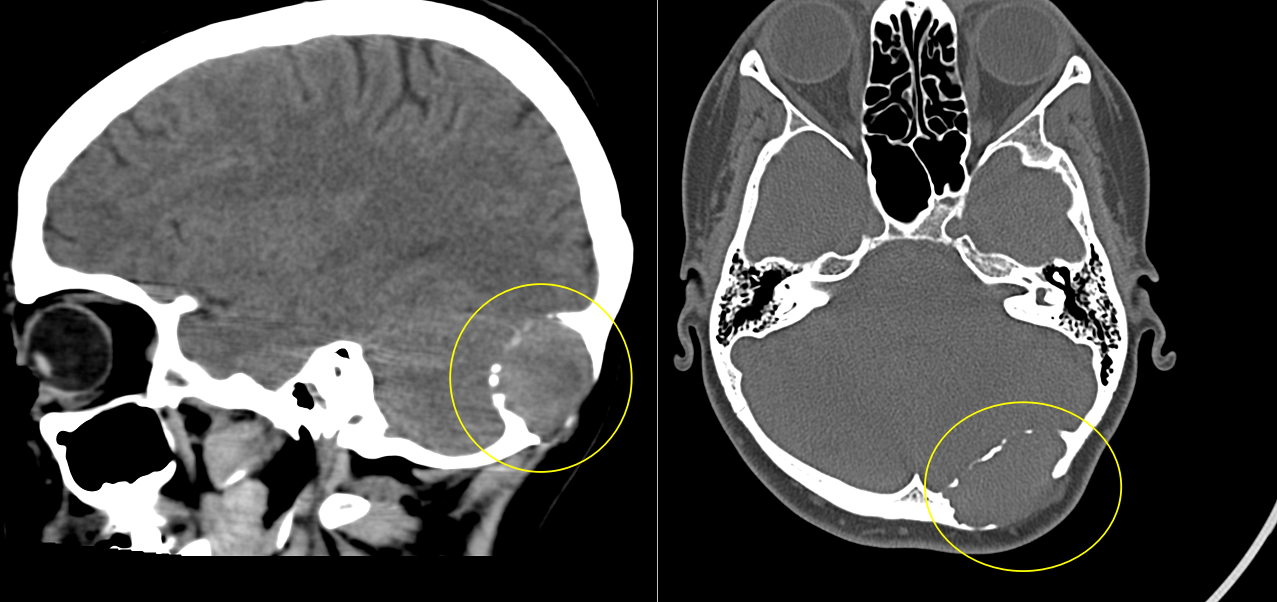

A. Imagistică:

- Radiografie craniană: utilă pentru modificări osoase evidente.

- CT cranian cu reconstrucție 3D: evidențiază detalii osoase.

- RMN cerebral cu contrast: evaluează extensia intracraniană, vasele și nervii implicați.

C. Cordomul

Tumoră rară, malignă, ce derivă din resturi embrionare ale notocordului.

Apare frecvent la nivelul clivusului (baza craniului).

Se dezvoltă lent, dar are potențial invaziv.

Simptome: durere, pareze oculomotorii, tulburări de deglutiție.

Tratament: rezecție chirurgicală maximală + radioterapie stereotactică – protonoterapia sau radioterapia cu ioni de carbon.

B. Condrosarcomul

Tumoră malignă ce derivă din țesut cartilaginos.

Frecvent localizat la baza craniului (clivus, sfenoid).

Simptome: cefalee, diplopie, afectarea nervilor cranieni.

Creștere lentă, dar invazivă.

Tratament: excizie chirurgicală completă + radioterapie postoperatorie.